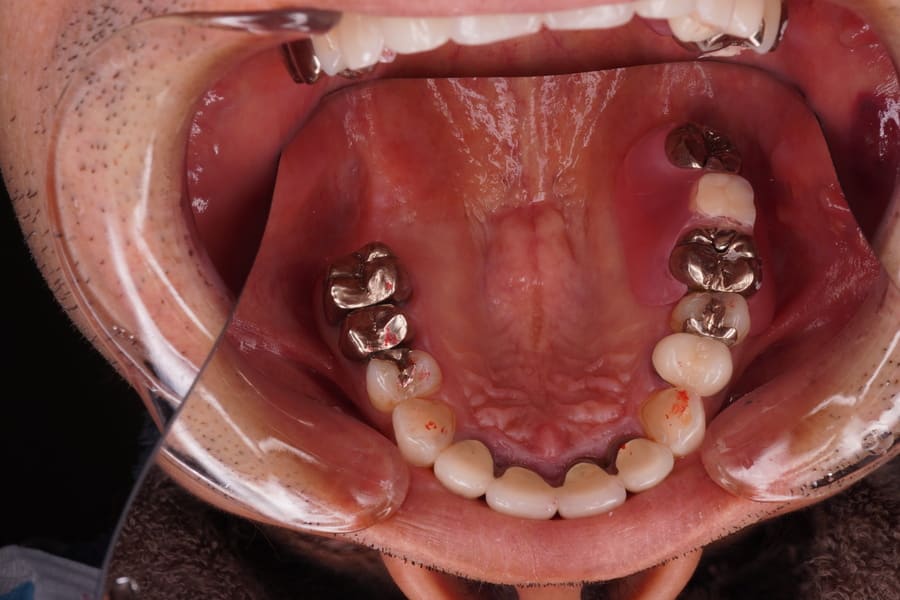

After

左上7番欠損。 昔、入れ歯を作ったが近年使用していない。 歯周組織は最大ポケット3㎜でエックス線所見においても問題となる骨欠損は認められず左上6,8番ともブリッジ、義歯の支台歯として適応可能と判断した。 補綴装置としてブリッジ、義歯、インプラントいずれも適応可能であった。 患者さんの希望は、補綴物や骨を出来るだけ傷つけない治し方であった。 各種補綴方法の利点・欠点・特徴・金額を説明した後、 患者さんの希望として、出来るだけ違和感がない物、見た目もあまり金属等で目立たないもの、落としても壊れにくい物であった。 これらのことを総合的に検討して、ノンメタルクラスプデンチャーの適応を提案し了解が得られたので製作することとした。 各種あるノンメタルクラスプデンチャーの材料の種類として、比重が軽く生体親和性が高く比較的柔らかいポリプロピレン系を選択した。 理由として一歯欠損のため義歯のたわみが起こりにくいこと、そのことによる適合不良が起こりにくいこと。上顎が対象のため軽めの材料が適していることなどである。 左上6番遠心、8番近心に明瞭なレストシートを設定することとした。 日本補綴歯科学会発行のノンメタルクラスプデンチャーガイドラインにも義歯の安定のためにメタルレストの重要性が述べられている。 まず歯周基本治療を行い歯周組織の安定を図った。 口腔内にて冠の一部を切削・研磨して明瞭な広さ、深さのレストシートを設置した。 ろう義歯試適を行い咬合のずれ等問題がないことを確認した、 患者さんに鏡を見ながら着脱の練習をしていただき、ご自身での取り扱いが可能であることを確認した。 1週間後に来院していただき、各種チェックを行い、粘膜面に痛みがあったため適合検査を行い過圧部分があったため調整を行った。咬合に問題はなかった。 1週間後に痛みが出ていたため2週間後にリコールを行いさらに粘膜面の調整を若干行った。 その後、2週間後にリコールを行い問題がないことを確認した。 ノンメタルクラスプデンチャーによる欠損補綴 |